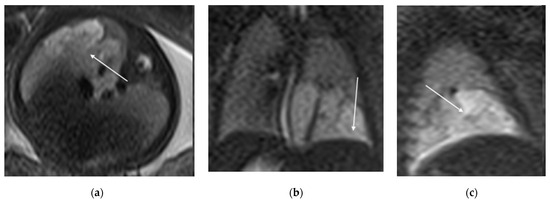

Figure 5. T2 HASTE axial plane (a), coronal (b) and sagittal (c): shows a multicystic brilliant formation (white arrow), at the level of the right and middle lower lobes. The lesion represents 55% of the right lung volume.